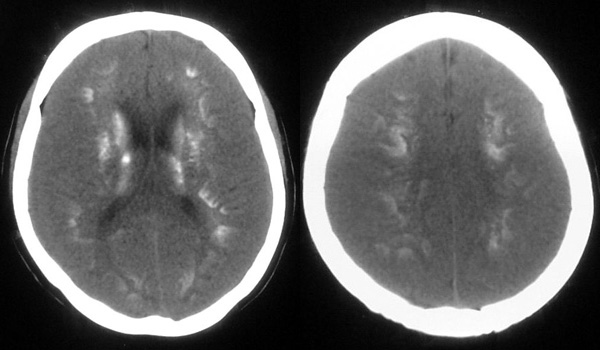

患者,女,49岁,头痛数年,有癫痫病史,无外伤史。

甲状旁腺低下:颅脑 ct 可见以基底节为中心的双侧对称性、多发性、多形性脑钙化的特点。除苍白球外,可广泛分布于壳核、尾状核、小脑齿状核、丘核、内囊及脑皮质、白质等处。